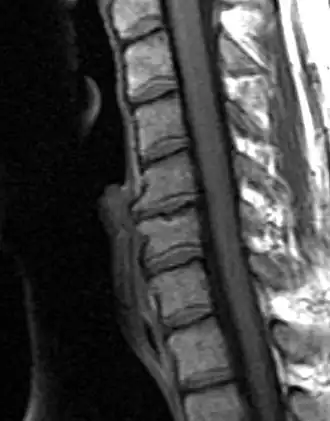

![]() Дегенеративно-дистрофическое заболевание диска, C5-C6 с остеофитами | |

Типичными рентгенографическими данными ДДЗД являются черные диски, сужение дискового пространства, вакуумные диски, склероз конечной пластинки и образование остеофитов[2][3].

Фиброхрящ вытесняет материал студенистого ядра, что является возрастным изменением. Также может наблюдаться усыхание студенистого ядра, которое вызывают пролапс или сгибание фиброзного кольца с образованием на краях между телами позвонков вторичного остеофита. К патологии ДДЗД относят протрузию, спондилолиз, смещение позвонков (спондилолистез) и стеноз позвоночного канала. Существует возможность разрыва фиброзного кольца, что приведет к грыже студенистого ядра.

Диагностика дегенеративно-дистрофического заболевания диска обычно состоит из анализа индивидуальной истории болезни пациента, физикального исследования, предназначенного для выявления мышечной слабости, болевого синдрома, определения объёма движения, и МРТ-сканирования для подтверждения диагноза и исключения других причин.